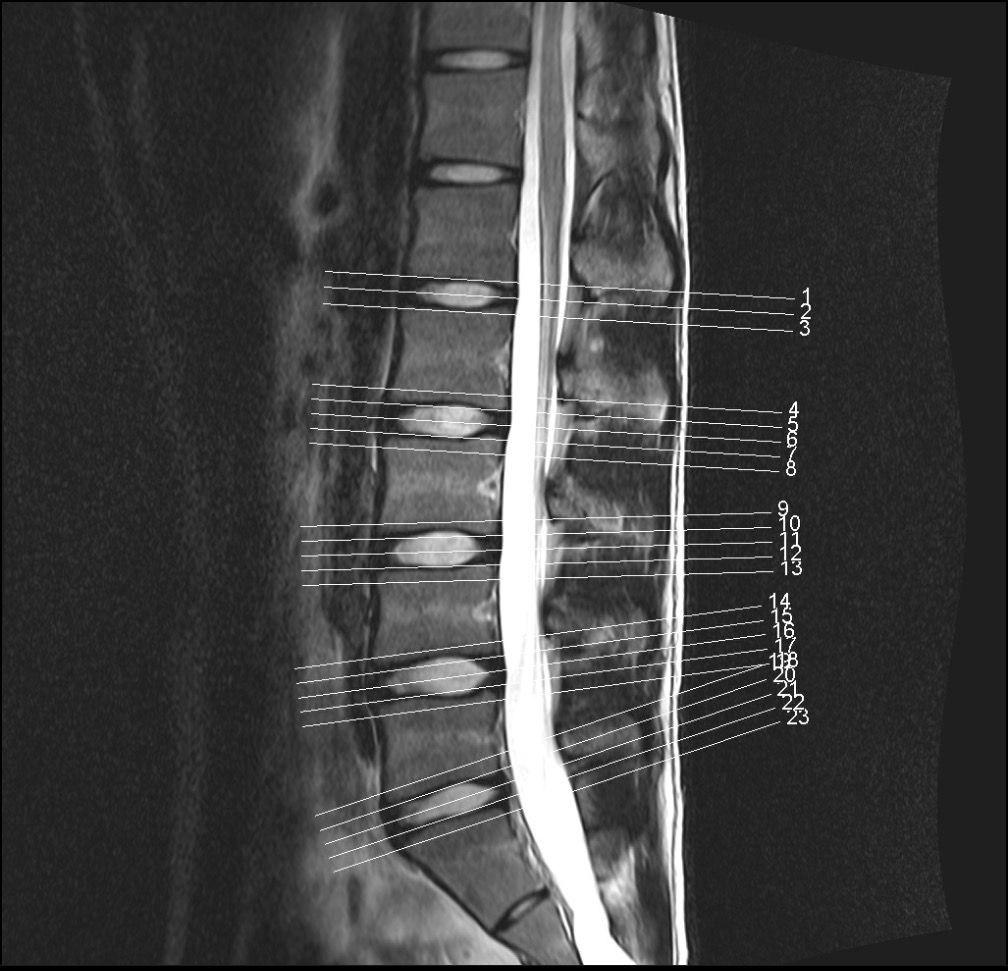

Mrl 보시고 확인좀 부탁드리겠습니다 교통사고가 나서 허리가 안좋아서 Mrl 촬영했습니다 근데 디스크가 있다고 합니다 한방병원에서는 있다고 하고

허리전문병원에서는 없다고 합니다

누구 말을 믿어야할지 모르겠어요 바쁘시겠지만 부탁드리겠습니다

mri상으로볼때에는 디스크가 약간 나와있는걸로보이지만 신경을 자극한다거나 다른문제는없어보이는데요 일단 불편감이지속되고있다면 근육의긴장이나 염증으로인해서 그러는증상일수도있습니다

병원마다 MRI 결과를 다르게 보는 이유로는 디스크가 살짝 튀어나와 있지만 신경을 누르지는 않거나 그 경계에 있다면 그럴 수 있으며 올려주신 MRI사진 같은 경우 단면 사진으로 단면사진만으로는 평가하기 힘들 것으로 생각되며 일단 올려놓으신 영상만 보았을때는 큰 문제는 없는걸로 보이며 자세한 상태는 영상을 가지고 전문 병원에 방문하시어 제차 검사 받아보시는게 좋을 것으로 생각됩니다.

올려주신 사진상에서 허리 아래부위에 존재하는 디스크가 약간의 돌출이 보이는데요, 신경을 압박하는 것처럼 보이지는 않습니다.

디스크 돌출이나 경미한 추간판 탈출증으로 보이는데요, 각 병원에서 견해에 따라 허리디스크로 진단하거나 하지 않는 것으로 보입니다.